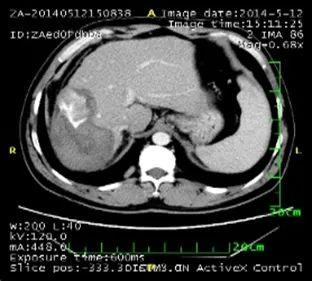

2. 肺部病灶治疗前后核磁对比:

肺部转移病灶在用药后2个月明显缩小,4个月后病灶基本消失。

治疗前

治疗2个月

治疗4个月

治疗6个月

治疗16个月